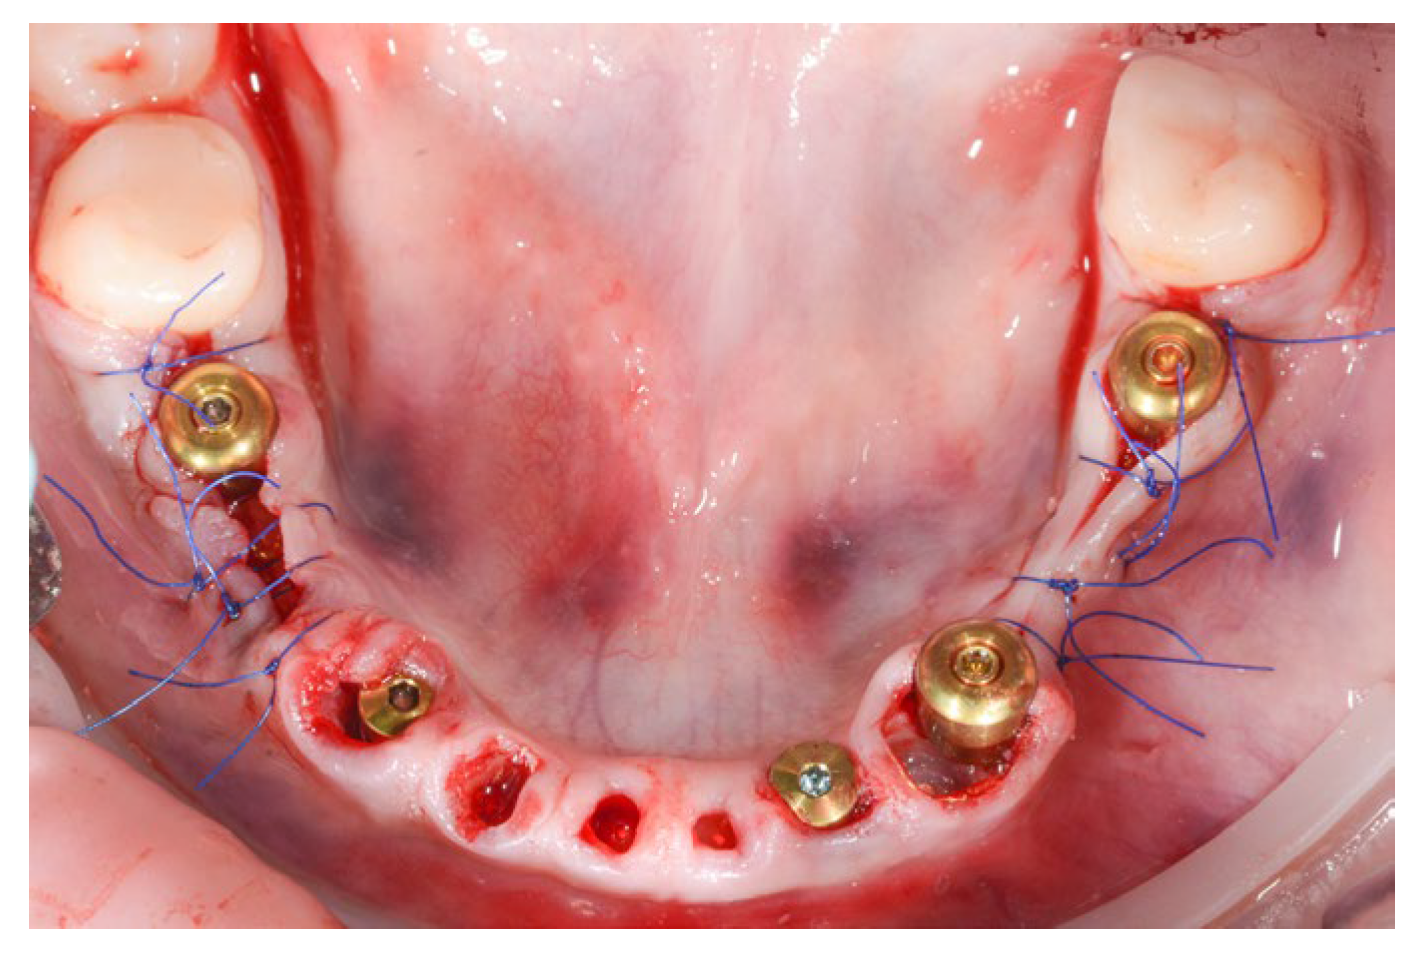

Figure 12.

Post-operative aspect of mandibular implant placement and PET for 71, 72, 73, 81, 82 and 83.

The PET technique was used for the remaining mandibular incisors and canines after previous endodontic treatment (Figure 12).

For the mandibular arch, five MIS V3 implants were inserted with guided surgery in the position of 36, 34, 32, 43 and 45, all with 40 Ncm primary stability. We used three MU abutments and two Connect abutments for a passive fit of the future screw-retained bridge and also to have the benefits of the one abutment one time concept.